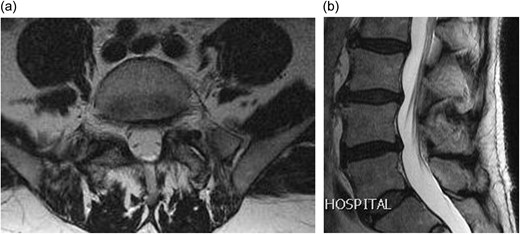

CLINICAL DETAILS

A 66-year-old male presented to our institution with 12 months history of severe back pain and left leg pain in L5/S1 distribution. On examination he had a normal neurology except for a dull left ankle jerk. Magnetic resonance imaging (MRI) of his lumbo-sacral spine showed a left L5/S1 synovial cyst (Fig. 1a and b). The findings and management options were discussed with the patient, who decided for a surgical option. However in view of his recent cardiac history it was decided to see him again in clinic in 6 months’ time. After reviewing him in clinic, he was added to the surgical waiting list and as his MRI scan was a year old, fresh set of scans was requested nearer to his operation date. Surprisingly his repeat MRI showed complete resolution of the L5/S1 synovial cyst (Fig. 2a and b).

(a) Axial T2 weighted MRI showing complete resolution of the synovial cyst; (b) sagittal T2 weighted MRI showing complete resolution of the synovial cyst.